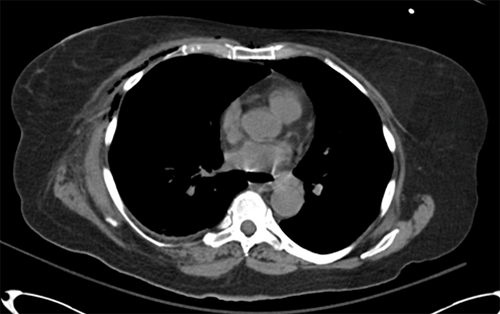

Initial computed tomography (CT) study of the abdomen revealed several large gas and fluid collections in the pelvis, intraperitoneal inflammatory changes in the right lower quadrant, and wall thickening throughout the sigmoid colon with adjacent fluid collections. There was a large 4 × 8 × 14 cm gas and fluid collection in the abdominal wall musculature interposed between the internal and external oblique muscles (Figure 1 and Figure 2). A CT of the thorax revealed extensive gas in the right chest wall with pectoralis, serratus anterior muscle, and subcutaneous tissue involvement, suggesting necrotizing soft tissue infection (Figure 3). Physical exam revealed induration and erythema extending from the right flank to the epigastrium and down to the right lower quadrant without obvious necrotic skin or soft tissue.

Figure 3. Axial CT of Thorax. Published With Permission

Gaseous collection seen in anterior right chest wall.